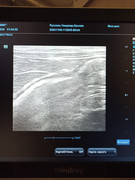

Сделали повторное узи 22.11. 2024 (первое было 09.11.2024). Высылаю фото и заключение.

Теперь ставят гидрометру и эндометрит. По мочевому мочекаменную.